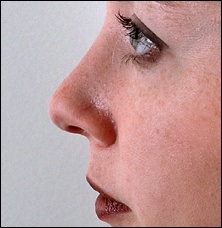

A fénykép a bal oldalon mutatja egy ember tipikus megnövekedett nazális gerinc. Ez jelentősen növeli az orrát előre. A fénykép után a művelet ugyanaz az ember nagyon jól néz ki.

Ebben a beteg, ott van a hatás a „kötés” a felső ajak. Photo fenti elégedett üzemeltetés előtt. Fekete jelzi a helyzetét az első kiálló orr-gerinc. A kék vonalat húzott a jobb megítélése a profilt. Ha a hatása „árukapcsolás” a felső ajak vonal irányította a profilját Vered és legfeljebb az alap az orr.

Az operáció utáni képek labrum irányban függőlegesen felfelé.

A nő látható a felső fotó túl kiálló orrát. Ezt segíti elő a túlzott acanthion. Ezen kívül volt egy jelentősen nőtt a felső ajak. Amint azt a jogot, fotó, rövidítést követően az orrhegy és változtatni az alakját a felső ajak volt a hatása lerövidíti az orrát. Meg kell jegyezni, hogy ebben az esetben a hosszúkás gerinc nem vezet túlzott nyitó columella.